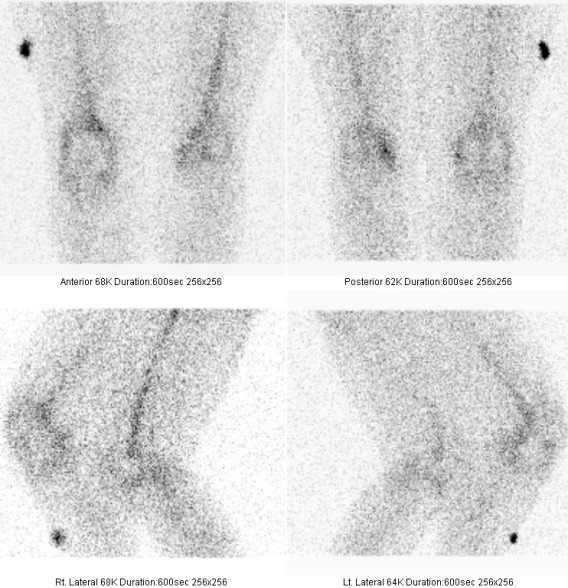

Cílené statické scintigramy (obr.1, 2a, b, 3 a 4) jsme provedli po i.v. podání 700 MBq

Medical) na dvouhlavé tomografické scintilační kameře E.CAM firmy Siemens v přední, bočních a zadní projekci. Je patrné patologické zvýšení depozice radiofarmaka kolem tibiální komponenty TEP pravého kolena. Je také vyšší depozice radioindikátoru v mediálním kondylu tibie vlevo (nejspíše jako projev degenerativních, artrotických změn). Závěr: nález svědčí pro uvolňování tibiální komponenty TEP pravého kolenního kloubu. Osteomyelitidu nelze vyloučit.

/ Obr. č. 1: Statické scintigramy skeletu kolenních kloubů v přední projekci /

/ Obr. č. 2a, b: Statické scintigramy skeletu kolenních kloubů v zadní projekci /

/ Obr. č. 3: Statické scintigramy skeletu kolenních kloubů v boční projekci /

/ Obr. č. 4: Statické scintigramy skeletu kolenních kloubů v boční

projekci /